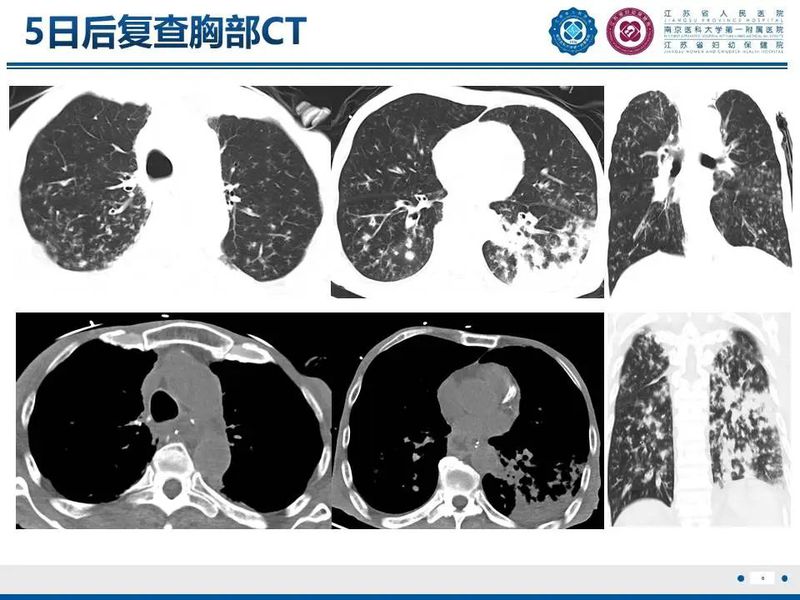

肺炎克雷伯杆菌

来源:江苏省人民医院放射科